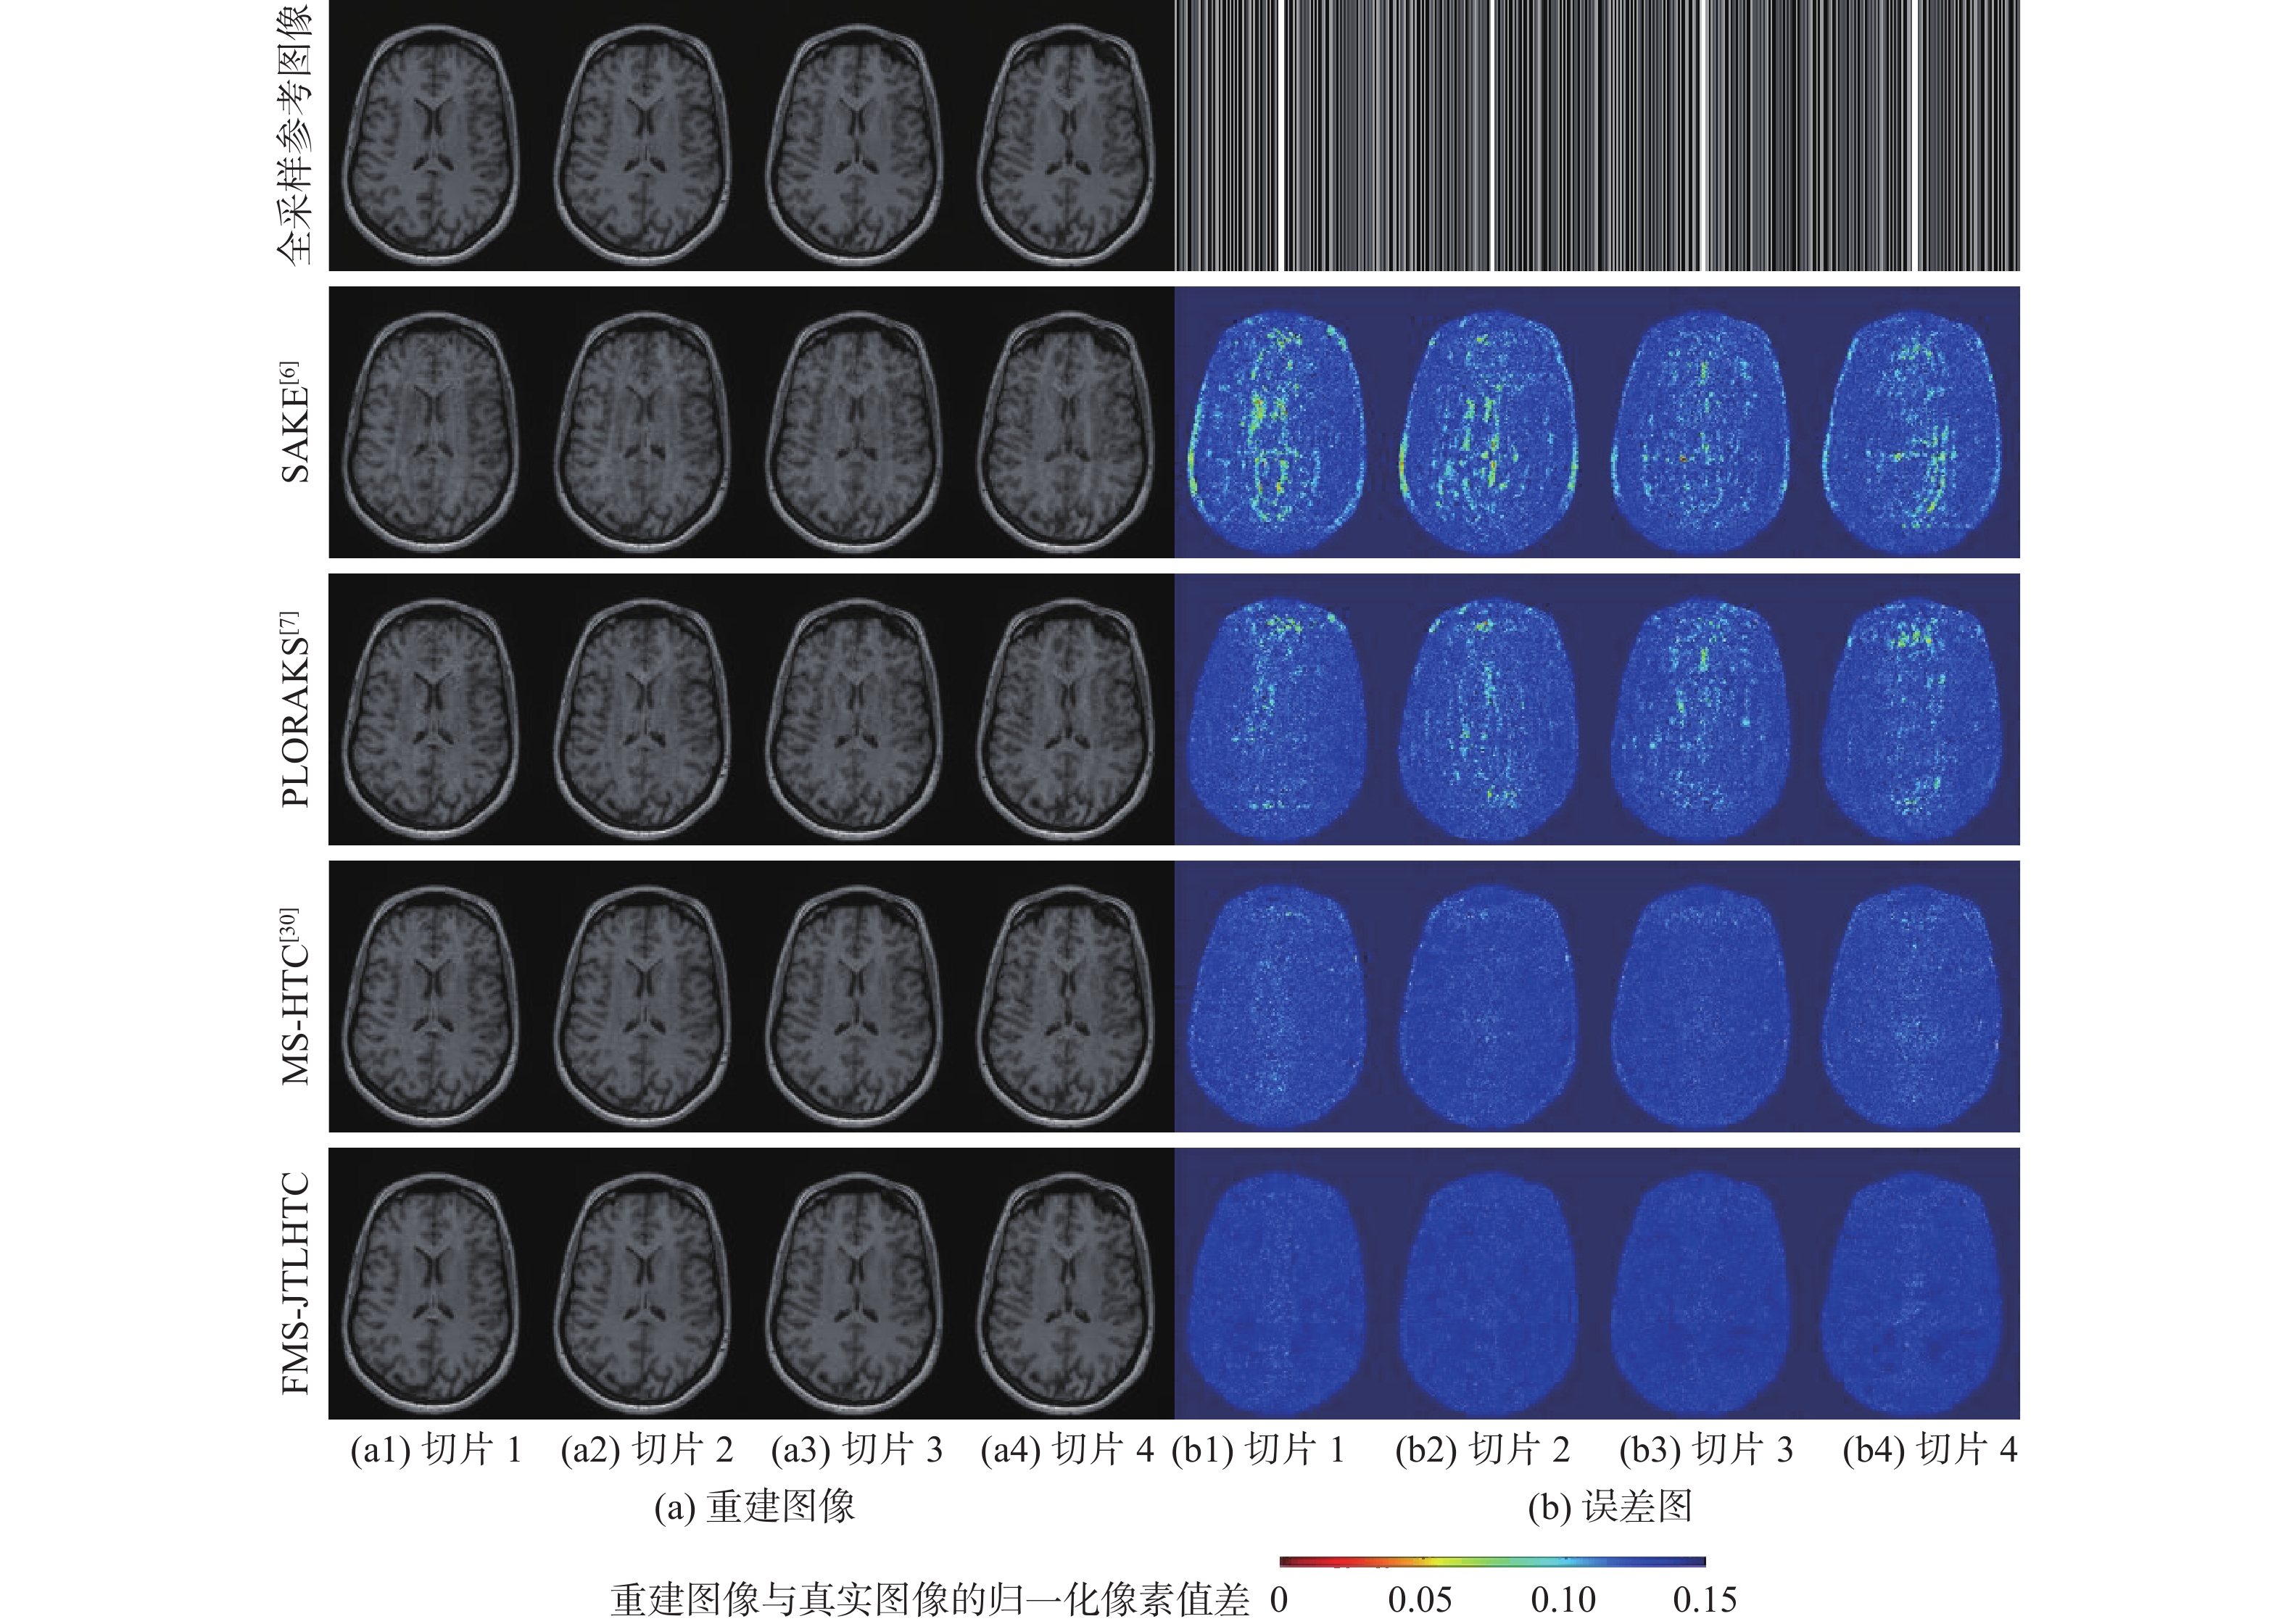

A low-dose CT deep unfolding network based on a sparse transform priors constrain

WANG Yue, ZHANG Xiong, SHANGGUAN Hong, CUI Xueying, ZHANG Pengcheng, GUI Zhiguo

2026, 52(4): 1199-1210. doi: 10.13700/j.bh.1001-5965.2024.0049

Abstract:

Deep iterative unfolding networks have garnered a lot of attention lately because of their great learning capabilities and good interpretability. The regularization terms in existing CT image reconstruction methods mostly focus on information within a specific domain, leading to issues such as edge blurring and information loss in the reconstructed results. Therefore, a sparse transform prior constrain based deep unfolding network is proposed for sparse-view CT reconstruction. Two regularization terms with complementary information—transform-domain sparse regularization and pixel-domain consistency regularization—are created in consideration of the important roles that both pixel-domain and transform-domain information play in picture reconstruction. Based on these, the objective function for sparse-view CT reconstruction is redesigned. Furthermore, a new deep unfolding network for iterative reconstruction of low-dose CT is created by mapping a set of constraint relationships established from an iterative optimization solution for the constructed objective function. Experimental results demonstrate that the algorithm presented in this paper achieves a great improvement on average peak signal to noise ratio (PSNR) and visual information fidelity (VIF) compared to the classical FISTA algorithms.